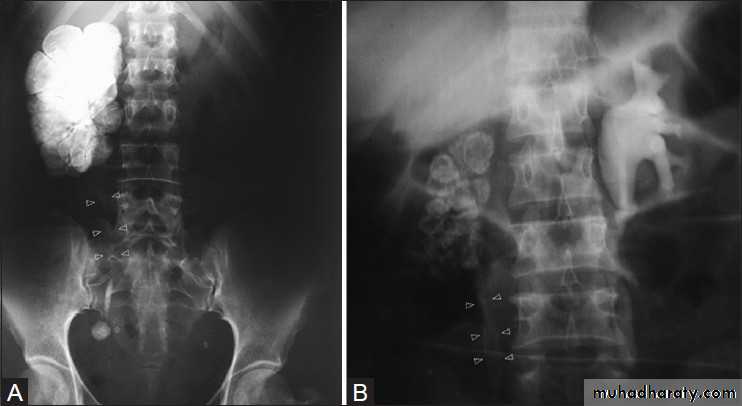

IVU findings include:

1.Initial changes irregularity of the calyx then later cavity filled with contrast2.Calcified irregular foci

3.Autonephrectomy

4.Multiple strictures in PCS and ureter

5.Thick wall small volume urinary bladder